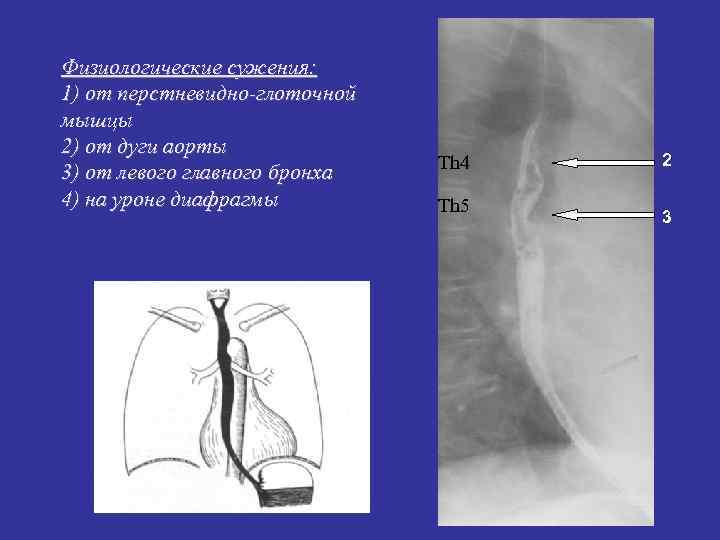

Физиологические сужения: 1) от перстневидно-глоточной мышцы 2) от дуги аорты Th 4 2 3) от левого главного бронха 4) на уроне диафрагмы Th 5 3